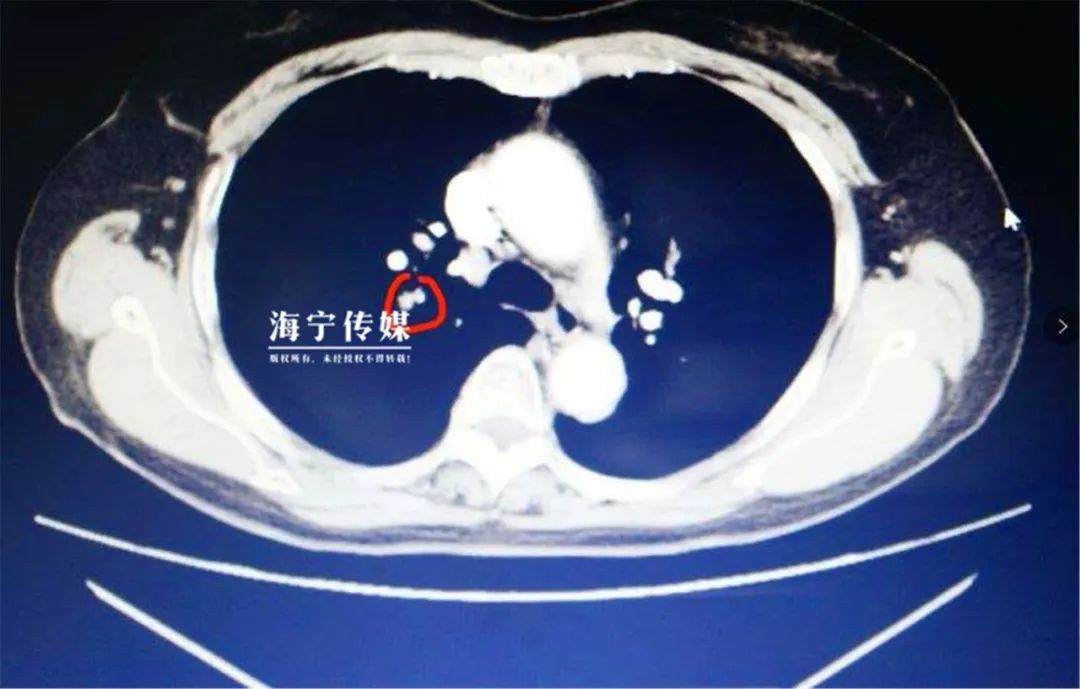

徐晗飞连忙给吴阿姨安排了心电图、血常规、胸肺部CT等检查。在下肢动静脉B超中显示,吴阿姨患有右下肢肌间小腿静脉血栓,在肺动脉CTA检查报告中显示,她还患有两侧肺动脉栓塞,需要立即住院接受治疗。